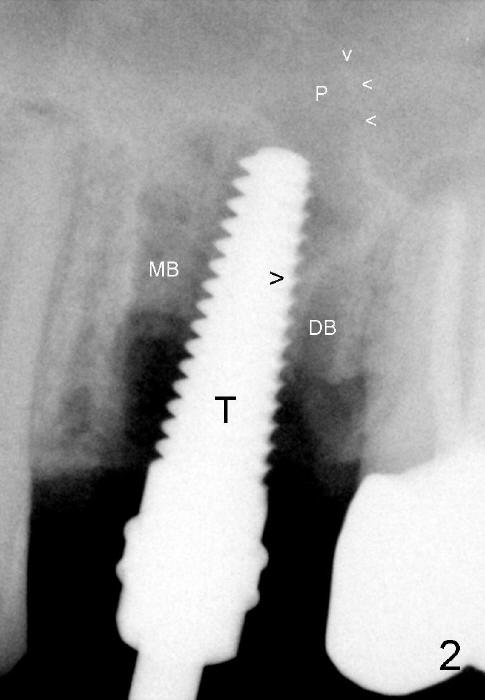

A 4.5x17 mm tap (Fig.2 T) is inserted 8 mm deep with binding to the septum. It appears that the sinus floor (black >) has been penetrated (in fact the septum height is ~5 mm), but the osteotomy has not reached the apex (white >) of the palatal (P) socket.  Then the tap is advanced ~ another 3 mm.  MB: mesiobuccal; DB: distobuccal socket.